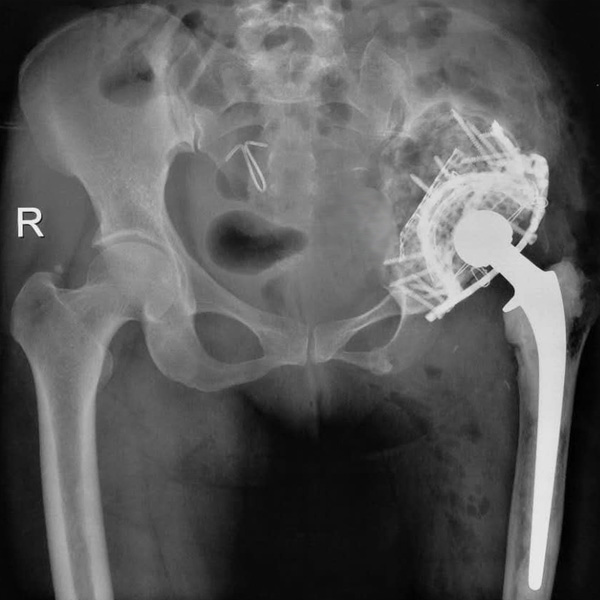

手術(shù)后手術(shù)前

髖關(guān)節(jié)翻修

患者蘇某,女性,11年前因“左髖關(guān)節(jié)屈曲攣縮畸形”行左側(cè)人工全髖關(guān)節(jié)置換,近來(lái)感覺左髖關(guān)節(jié)疼痛,不敢行走,經(jīng)“攜生醫(yī)療平臺(tái)”就診于哈......